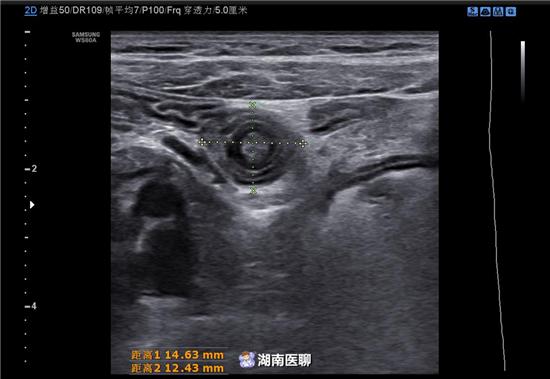

肠痉挛在超声上表现为直径小,类同心圆征或“向日葵征”,直径常小于20mm,肠管蠕动正常或活跃,肠壁无水肿,加压探头与持续观察可见类同心圆征或“向日葵征”消失。

(图为B超下发现的肠痉挛)